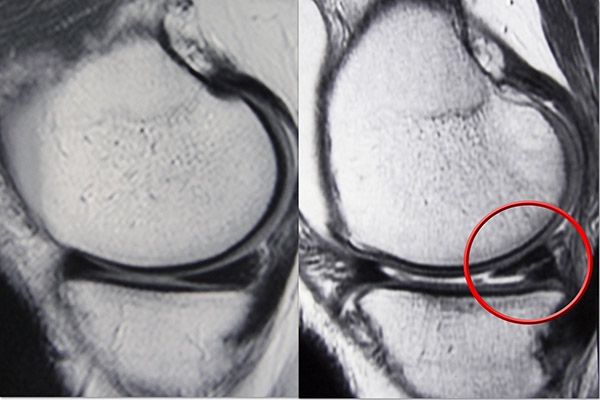

Μεταξύ της κνήμης και του μηριαίου οστού υπάρχουν δύο σφηνοειδή μαξιλαράκια: ο έσω μηνίσκος και ο έξω μηνίσκος. Οι μηνίσκοι λειτουργούν ως αμορτισέρ και παρέχουν επίσης σταθερότητα στην άρθρωση του γόνατος.

Υπάρχουν τρεις ζώνες του μηνίσκου με διαφορετικές ποσότητες ροής αίματος που επηρεάζουν την επούλωση:

Η κόκκινη-κόκκινη ζώνη έχει τη μεγαλύτερη παροχή αίματος και ικανότητα επούλωσης, ενώ η λευκή-λευκή ζώνη έχει περιορισμένη παροχή αίματος και χαμηλή δυνατότητα επούλωσης.